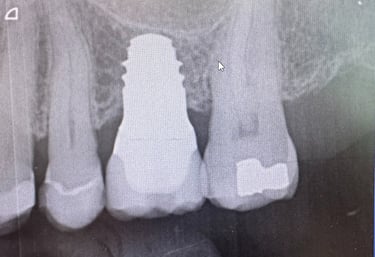

Hammasimplantti on titaaninen tai keraaminen 'ruuvi' joka asetetaan luuhun. Tämän varaan voidaan valmistaa yksilöllinen hammas.

Mielestäni kyllä. Ja siksi käytän vain Straumann -implantteja. Niiden avulla saadaan paras mahdollinen rakenne ennustettavalla luutumisella. Myös tärkeää on että tulevaisuudessa on osia tarvittaessa saatavana. Maailmassa on noin 600 eri implanttimerkkiä käytössä ja olen valinnut Straumann implantit juuri näistä syistä. Straumann implantit on olleet kymmeniä vuosia markkinoilla ja tutkimus niiden osalta on perusteellista.